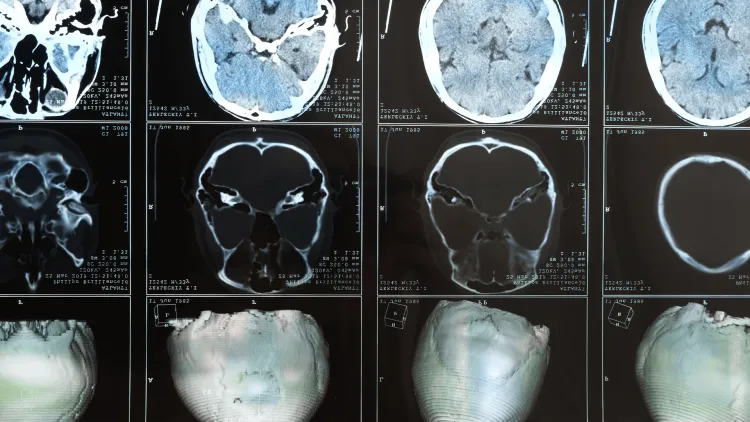

Radiation therapy has long been part of the default treatment for patients with brain metastases—tumors that started somewhere in the body and spread to the brain. But what if it didn’t have to be?

Radiation oncologist and Larner professor Chris Anker, M.D., and colleagues at the UVM Cancer Center (UVMCC) are challenging conventional wisdom with three integrated clinical trials aimed at reimagining care with more personalized, less intensive approaches:

• Funded through a UVMCC grant and led by Dr. Anker, the ACTION clinical trial starts the patient on several systemic therapies and monitors impact through MRI brain scans. If the brain metastases shrink, patients can defer or avoid radiation.